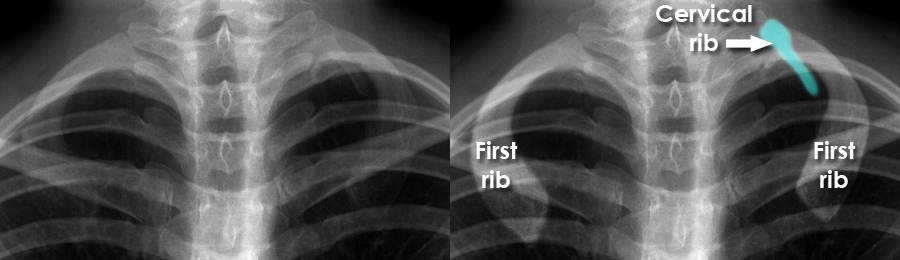

A cervical rib is an extra rib that arises from the seventh cervical vertebra in the neck. It is a congenital anatomical variation present at birth and occurs in a small percentage of the population.

Diagnosis is usually made with X-ray or other imaging studies. Treatment depends on severity. Many patients improve with conservative management such as physiotherapy, postural correction, activity and/or ergonomic modification.